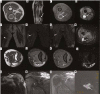

Material and methods: The conventional and diffusion magnetic resonance images (MRIs) of 42 patients operated for soft tissue sarcomas between June 2012 and March 2015 followed up with MRIs that were evaluated by 2 radiologists retrospectively. Diffusion MRIs were acquired at 4 different b-values (50, 400, 800, 1000 s/mm2). The lesions were classified according to conventional MRI findings as post-treatment changes and recurrent tumours.

Results: When the patient group with recurrent tumours was compared with the patient group with postoperative changes the ADC calculations were statistically significantly lower for the recurrent tumours at all b-levels (p < 0.001 for all b-levels). The sensitivity of b-50 values lower than 3.01 × 103 mm2/s in showing recurrent tumours was 100% and the specificity was 77.78%. The sensitivity of b-400 values lower than 2.1 × 103 mm2/s in showing recurrent tumours was 80% and the specificity was 96.3%. The sensitivity of b-800 values lower than 2.26 × 103 mm2/s in showing recurrent tumours was 100% and the specificity was 88.89%. The sensitivity of b-1000 values lower than 2 × 103 mm2/s in showing recurrent tumours was 93.3% and the specificity was 92.5%.

Conclusions: The ADC values obtained from diffusion-weighted images have high sensitivity and specificity in differentiating recurring soft tissue sarcomas during monitoring after treatment from postoperative changes.